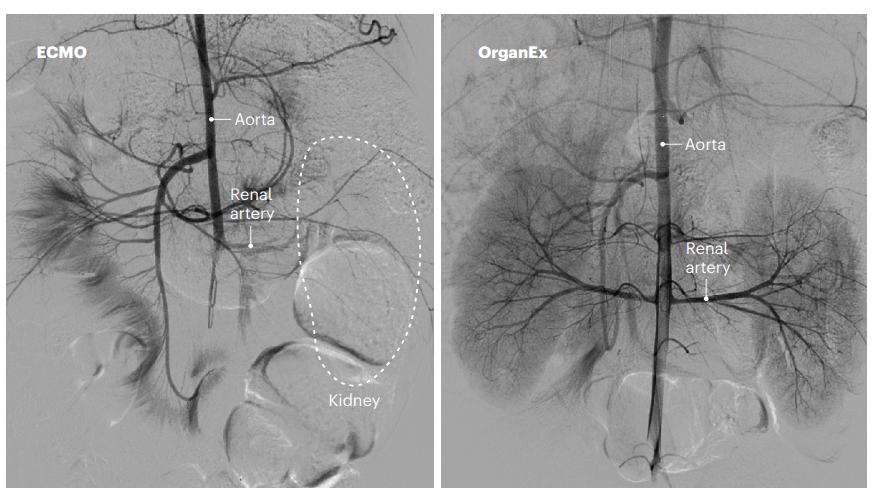

正是基于这个出发点,美国的研究团队近期开展了一项有针对性的实验。这项实验所采用的技术,是一种名为OrganEx的全新体外灌注系统。在实验之前,研究人员选择了一头健康的猪,对其进行深度麻醉后诱导其心脏病发作,从而抑制血液在猪体内的循环。猪身上的细胞由于长时间没有血液供氧的作用,出现了严重的缺氧问题,最后细胞大量死亡,各种器官也停止了运作,猪也没有了生命迹象。

在实验猪死亡一个小时之后,研究人员向猪的体内,注入了一种含有猪自身血液的特殊液体物质,同时还包括一种合成性血红蛋白、防止血栓形成和保护细胞的药物,然后持续观测死猪体内各种器官的变化情况。

没想到,在采用这样的措施6个小时之后,死猪体内的血液循环重新开始,很多细胞也恢复了活力,特别是猪的大脑、心脏、肾脏、肝脏等这些重要器官内的细胞重新开始运转。参与这项实验的科学家称,原本在正常状态下,不可能发生的细胞重启这种现象,通过这个实验实现了,从某种意义上来说,人类或许可以阻止细胞的死亡。